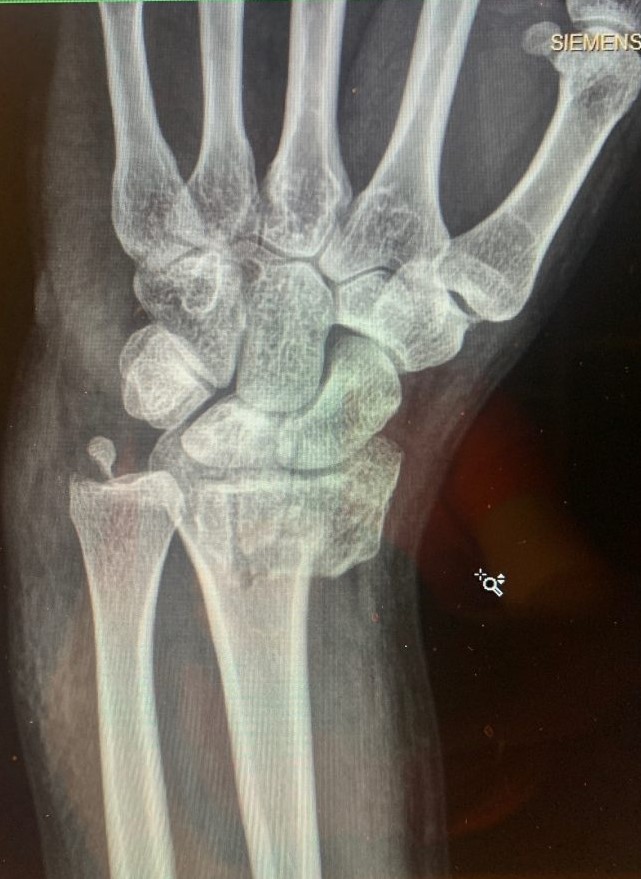

It all happened in a flash: I was biking on a warm Friday afternoon before Labor Day and all of a sudden I hit a pothole. I found myself lying in the street in agonizing pain with my left wrist tremendously swollen. At the emergency room, the doctors set my wrist somewhat in place and placed me in a cast up to my bicep. But they told me that I needed to have my wrist examined very soon (see photos 1, 2 and 3).

The following Wednesday I saw Dr. Aaron Daluiski after his office staff graciously squeezed me in. Dr. Daluiski said that I had suffered a very serious injury and unfortunately, my wrist would not heal well on its own. He recommended that I undergo surgery very soon, before the bones began to set on their own. Considering the gravity of my injury, Dr. Daluiski's staff was able to arrange for me to undergo surgery that Friday, less than 48 hours after I saw Dr. Daluiski.